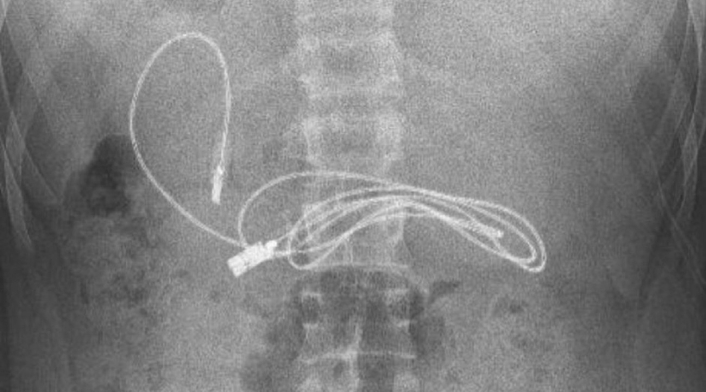

Pero algo curioso descubrieron los médicos, ya que encontraron un cable USB y una goma para el cabello en su interior.

Para poder extraer estos objetos, el joven fue intervenido quirúrgicamente. El gastroenterólogo que realizó la operación, publicó en sus redes sociales imágenes de hallazgo.

El doctor Yasar Dogan aseguró que se tuvo que hacer una endoscopia para poder llegar de una manera más fácil a los objetos, pero que fue complicada.

“Tuvimos dificultades para quitar el cable, ya que un extremo había pasado al intestino delgado". A pesar de las dificultades, la intervención fue un éxito, pues el paciente "fue enviado a casa con buena salud", afirmó.